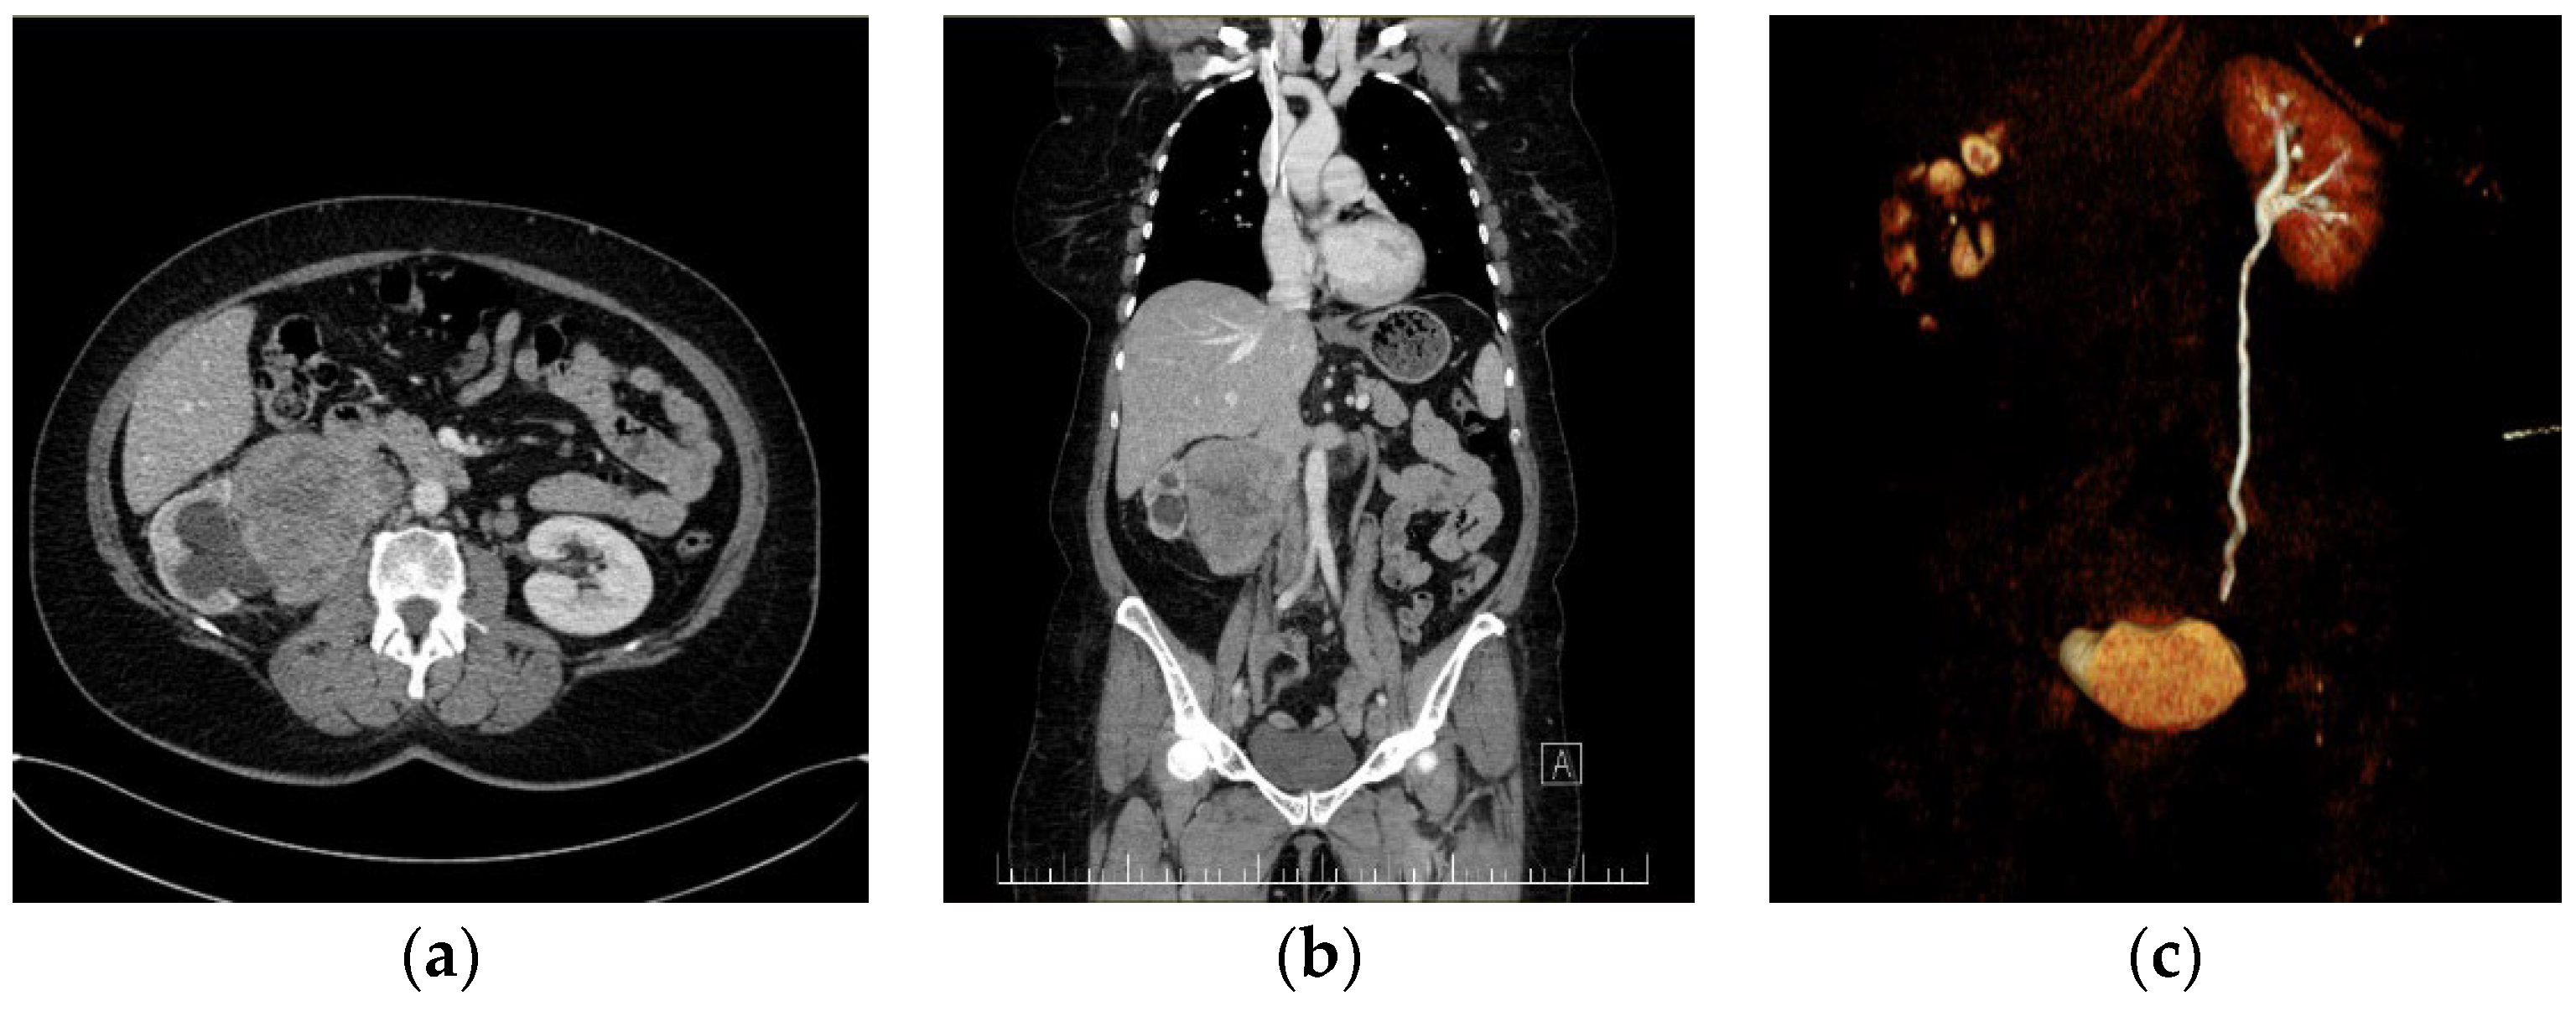

2. Case Report